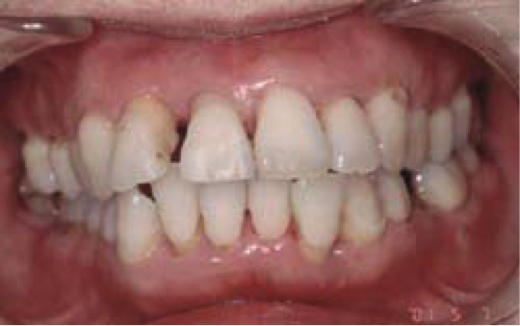

【女性(初診時37歳)非喫煙者】

全体的に6mm程度の歯周ポケットがあり、歯肉からの出血もひどく、冷たい水がしみる状態でした。

約4ヶ月にわたる初期治療の結果、写真のように健康な歯周組織に回復しました。歯周ポケットはほぼ3mm以内です。この後、さらなる予防のために歯並び矯正治療を行いました。